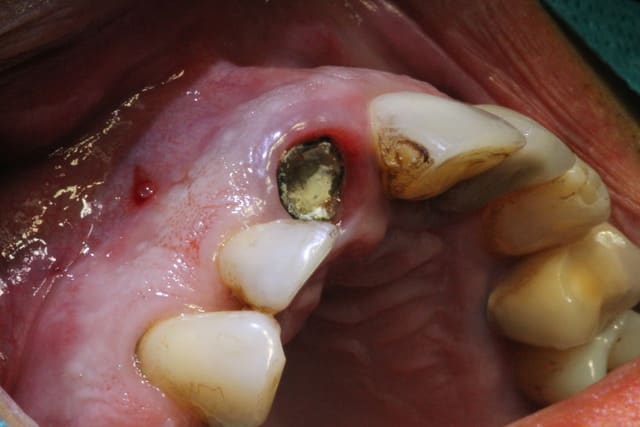

Tu prends qd même un risque d'implanter ds un site infecté ( fistule).

Pas d'infection en phase aiguë avant l'intervention, mais au vu de la fissure sur la racine et de la lésion osseuse, il devait y avoir quand même quelques bactéries.

J'ai bien cureté (manuel et rotatif), rinçage bétadine et métronidazole dans le mélange de biomatériaux.

Ça vaut ce que ça vaut, mais ça m'a paru correct sur le coup.

Ben sur la première photo , cela ressemble plus a une fistule qu'à un point d'anesthésie .

Je confirme, pas de fistule présente.